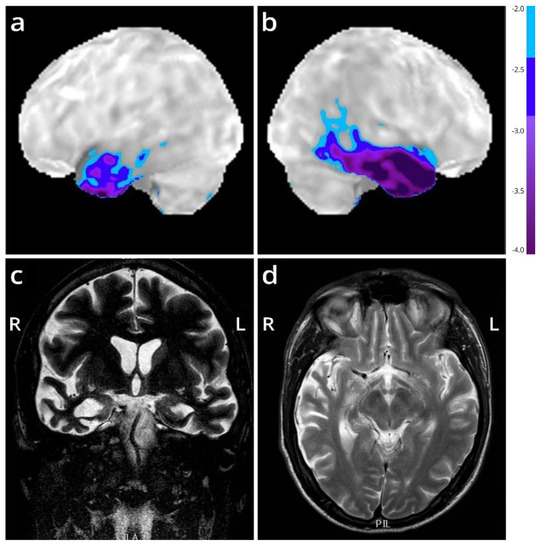

We present the autopsy case of a 60-year old man diagnosed at the age of 51 with the semantic variant of primary progressive aphasia. This was confirmed by MRI and

18F-FDG-PET, showing bilateral anterior temporal atrophy, which was more right-sided, as well as hypometabolism (

Figure 1). The patient showed prosopagnosia and problems with word retrieval and word comprehension. Later on, the patient also developed behavioral changes, such as obsessive-compulsive behavior, increased appetite with loss of table manners, discrete disinhibition, loss of decorum, and emotional indifference. Additionally, the patient displayed an inexhaustible glabellar reflex and extrapyramidal symptoms such as a discrete stooped posture and a decreased arm swing. The patient did not show any signs of motor neuron disease. There was a family history of Parkinsonism on the paternal side (